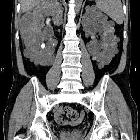

adult polycystic kidney disease (APCKD)

Autosomal dominant polycystic kidney disease (ADPKD), also sometimes more vaguely referred to as "adult polycystic kidney disease", is as the name would suggest, a hereditary form of adult cystic renal disease.

Macroscopically the kidney demonstrates a large number of cysts of variable size (from a few mm to many cms), in both the cortex and medulla. They are filled with fluid of variable color (from clear or straw colored to altered blood or chocolate colored to purulent when infected).

Radiographic features

Imaging of patients with autosomal dominant polycystic kidney disease can be challenging, simply due to the size and number of the cysts and associated mass effect on adjacent structures. It is potentially tedious, but necessary, to assess all cysts for atypical features, that may reflect complications (e.g. hemorrhage or infection) or malignancy (i.e. renal cell carcinoma) .

CT

CT is of course very sensitive to the diagnosis and excellent at characterizing renal cysts. Simple cysts appear as rounded structures with near water attenuation (~ 0 HU). The wall is very thin and regular, and are often imperceptible.

Cysts which have had internal complications may be hyperattenuating, with internal non-enhancing septations and/or calcifications.

A complex cystic mass with solid components or thick septa which enhance should be viewed with suspicion, and presence of a renal cell carcinoma (RCC) suspected (see Bosniak classification of renal cysts).